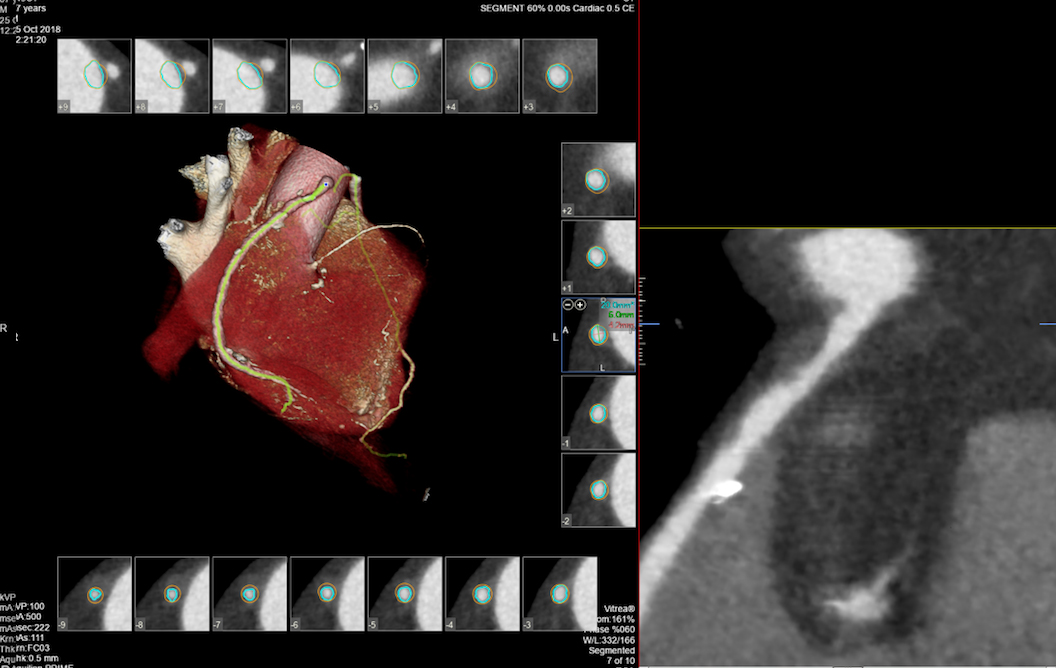

• MSCT koronarografija (prikaz krvnih žila srca CT-om, bez neugodnosti i komplikacija koje nosi klasična koronarografija), u saradnji s Poliklinkom dr.Al-Tawil